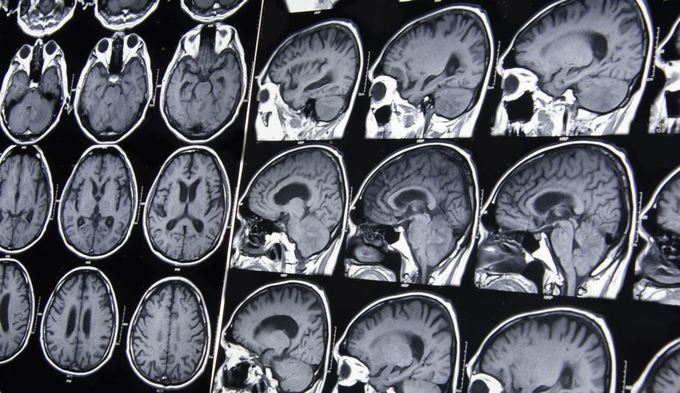

Cercetarea a inclus studierea scanărilor creierelor a 121 de femei şi 84 de bărbaţi cu vârstele cuprinse între 20 şi 82 de ani. Cercetătorii au creat un algoritm pentru a găsi o relaţie între vârsta unui om şi metabolismul creierului. Au găsit că acesta poate prezice vârsta cronologică bazându-se pe vârsta metabolică a creierului, relatează Live Science.